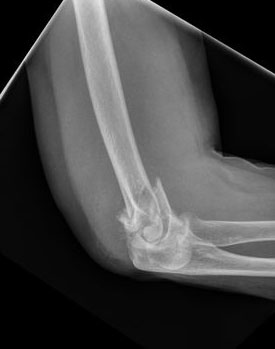

Fractura de húmero, intensa desviación de fragmentos

Fractura de húmero.

Fractura compleja de húmero.